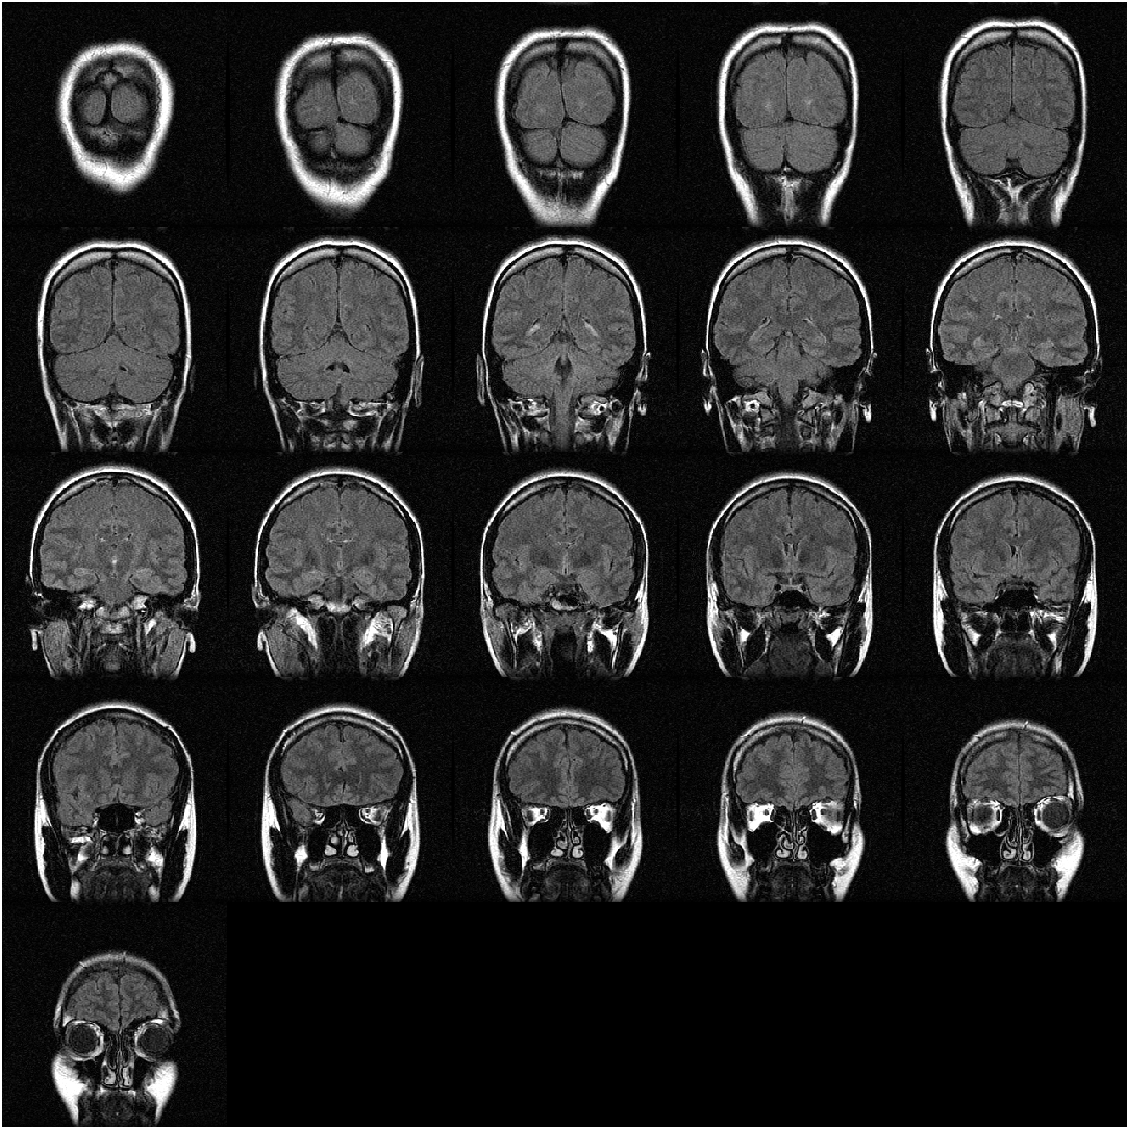

Example 1: create montage from multi-frame image (3-D array)

montage function can directly accept the image array as input. Take gray images, which have only one single color channel, as an example:

where code load mristack is used to load an MRI (Magnetic Resonance Imaging) data set, which only includes a 3-D uint8-class array mristack storing the pixel data of 21 gray images:

mristack 256x256x21 1376256 uint8

We can specify the number of images to be displayed by setting "Indices" property, like showing the first seven images for example:

img = montage(mristack,"Indices",1:7);